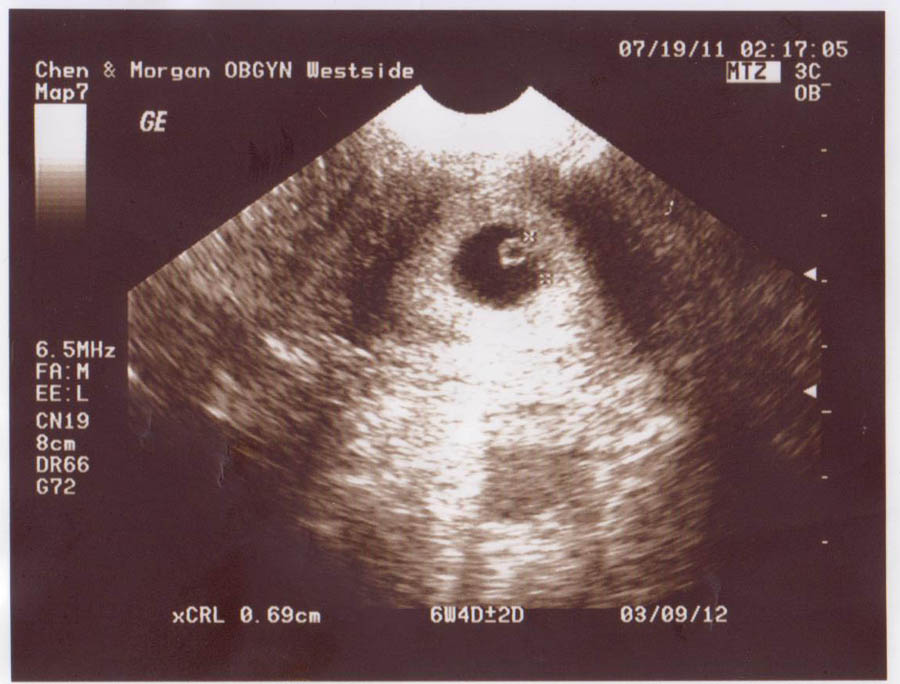

7 Weeks

6 Weeks